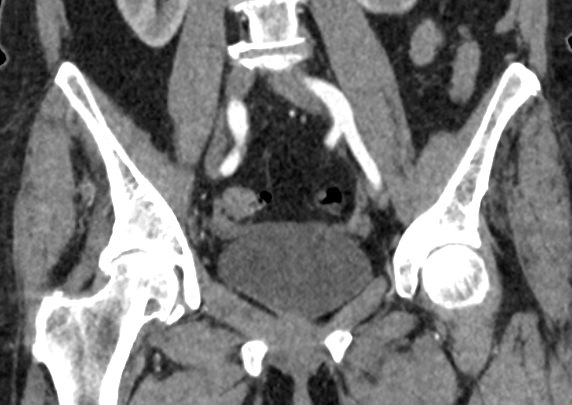

Мультиспиральная компьютерная томография органов малого таза включает в себя исследование женских половых органов (матка, яичники) или мужских половых органов (предстательная железа, семенные пузырьки, семявыносящие протоки), а также мочевого пузыря с мочеточниками на видимом протяжении, прямой кишки, тазовой брюшины, лимфатических узлов, мягких тканей малого таза.

В результате получаются снимки тончайших срезов исследуемой зоны с высокой степенью детализации, на основе которых производится объемная реконструкция органов малого таза, что позволяет проводить точную диагностику. Трехмерные модели дают информацию о пространственном расположении органов и патологических образований, что важно, например, при планировании оперативных вмешательств и в дальнейшем при оценке эффективности операции и проведенного лечения.

Мультиспиральная компьютерная томография используется для диагностики аномалий развития, травматических повреждений, воспалительных заболеваний и опухолевых процессов органов малого таза. Преимуществами данного исследования является высокая скорость сканирования и доступная цена. Однако в ряде случаев может быть более предпочтительно выполнение магнитно-резонансной томографии, которая обладает высокой чувствительностью и информативностью для обследования органов и мягких тканей малого таза. В клинике «Доступная медицина» МРТ малого таза можно пройти на нашем современном оборудовании экспертного уровня.